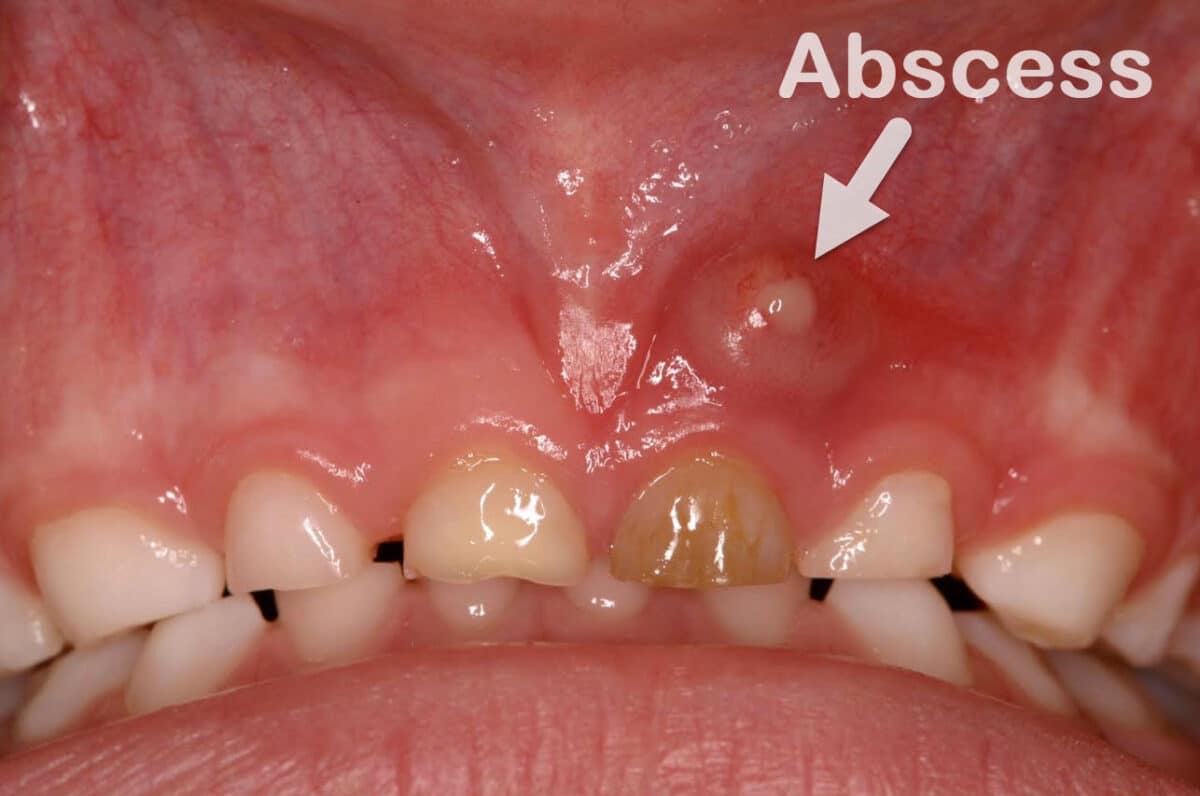

A dental abscess, also known as a tooth abscess, is a localized collection of pus caused by a bacterial infection in or around the tooth. According to the Mayo Clinic, it is essentially a pocket of pus that forms due to bacterial invasion, typically in the dental pulp, the innermost part of the tooth containing nerves, blood vessels, and connective tissue.

The Cleveland Clinic describes an abscess as a red, swollen bump, boil, or pimple-like formation in the gums, resulting from the body’s immune response to trap and fight the infection. If not addressed, the infection can spread beyond the mouth, leading to systemic issues.